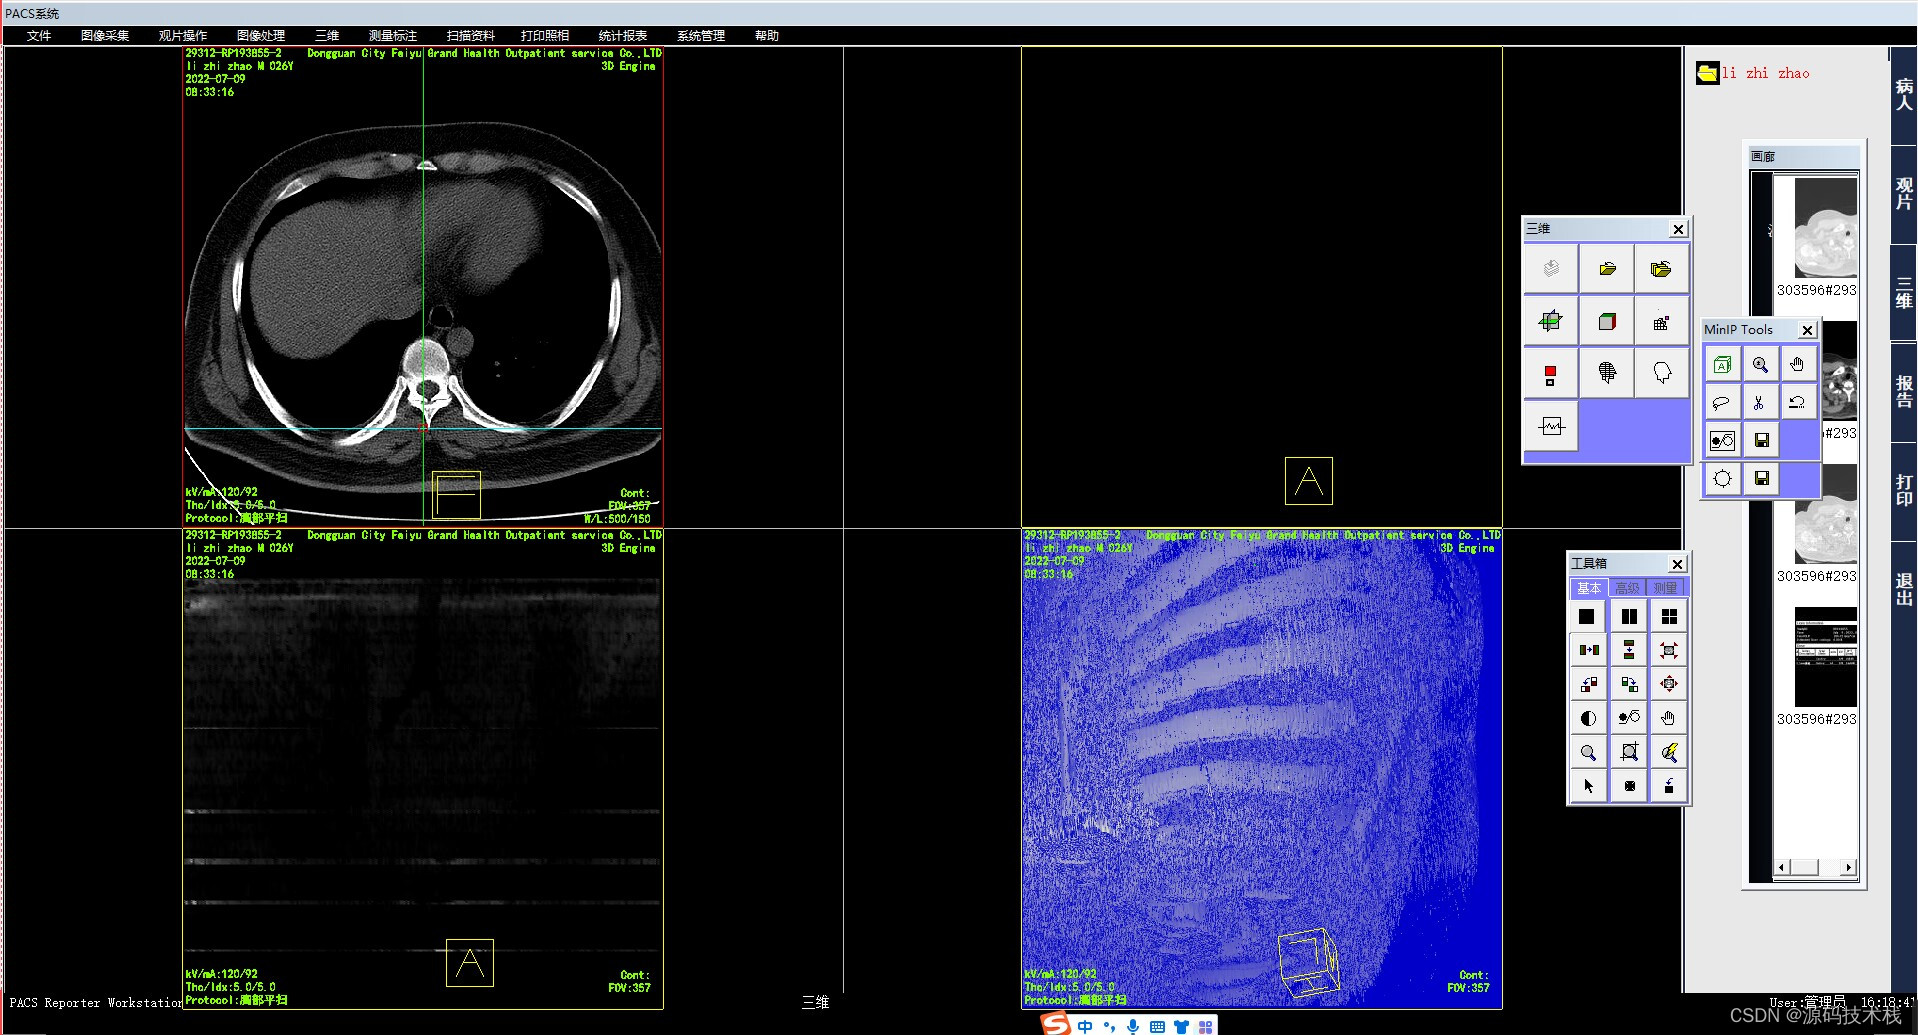

2.三维影像后处理:支持MPR、CPR、VRT、MIP、MinIP 、SSD、VE、CalSCore 三维图像处理;

13.支持MR和CT影像的定位线显示,并可以在定位线上直接定位到对应的断层;

15.支持多幅排列显示方式,自动窗宽窗位优化调整;